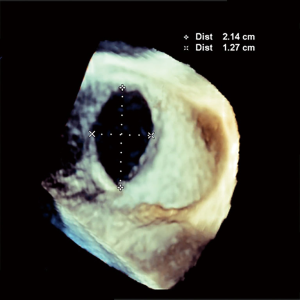

A 64-year-old female with no previous cardiac history progressively developed exertional pre-syncope and decreased endurance. Work-up revealed a dilated right ventricle and 3D-TEE illustrated a 21×13 mm secundum ASD (Figure 1). A 20 mm Amplatzer™ Septal Occluder (ASO) was selected for closure based on 3D-TEE sizing. During the procedure, RT3D-TEE aided in directly visualizing parallel apposition of the deployed left atrial ASO disk to the left atrial septum. After the right atrial disk was deployed, color Doppler imaging ensured appropriate device seal. Both left and right atrial disks were clearly identified with 3D right atrium and left atrium en face views confirming circumferential capture of the rim tissue (Figure 2). Adequate room posteriorly was ensured with 3D-TEE and helped show stability post-release with no evidence of encroachment into the aorta anteriorly.